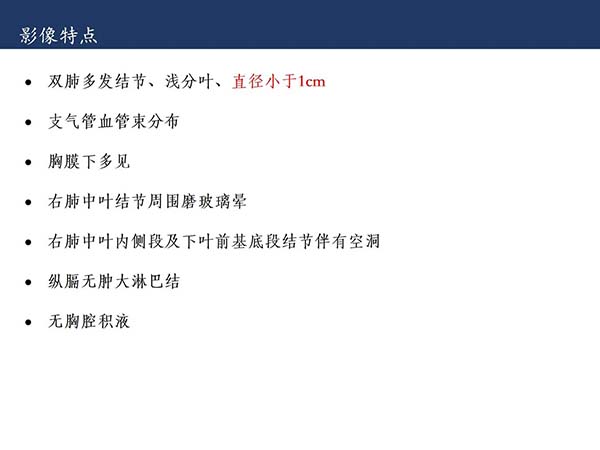

【杨柳科普】肺上皮样血管内皮瘤的影像表现